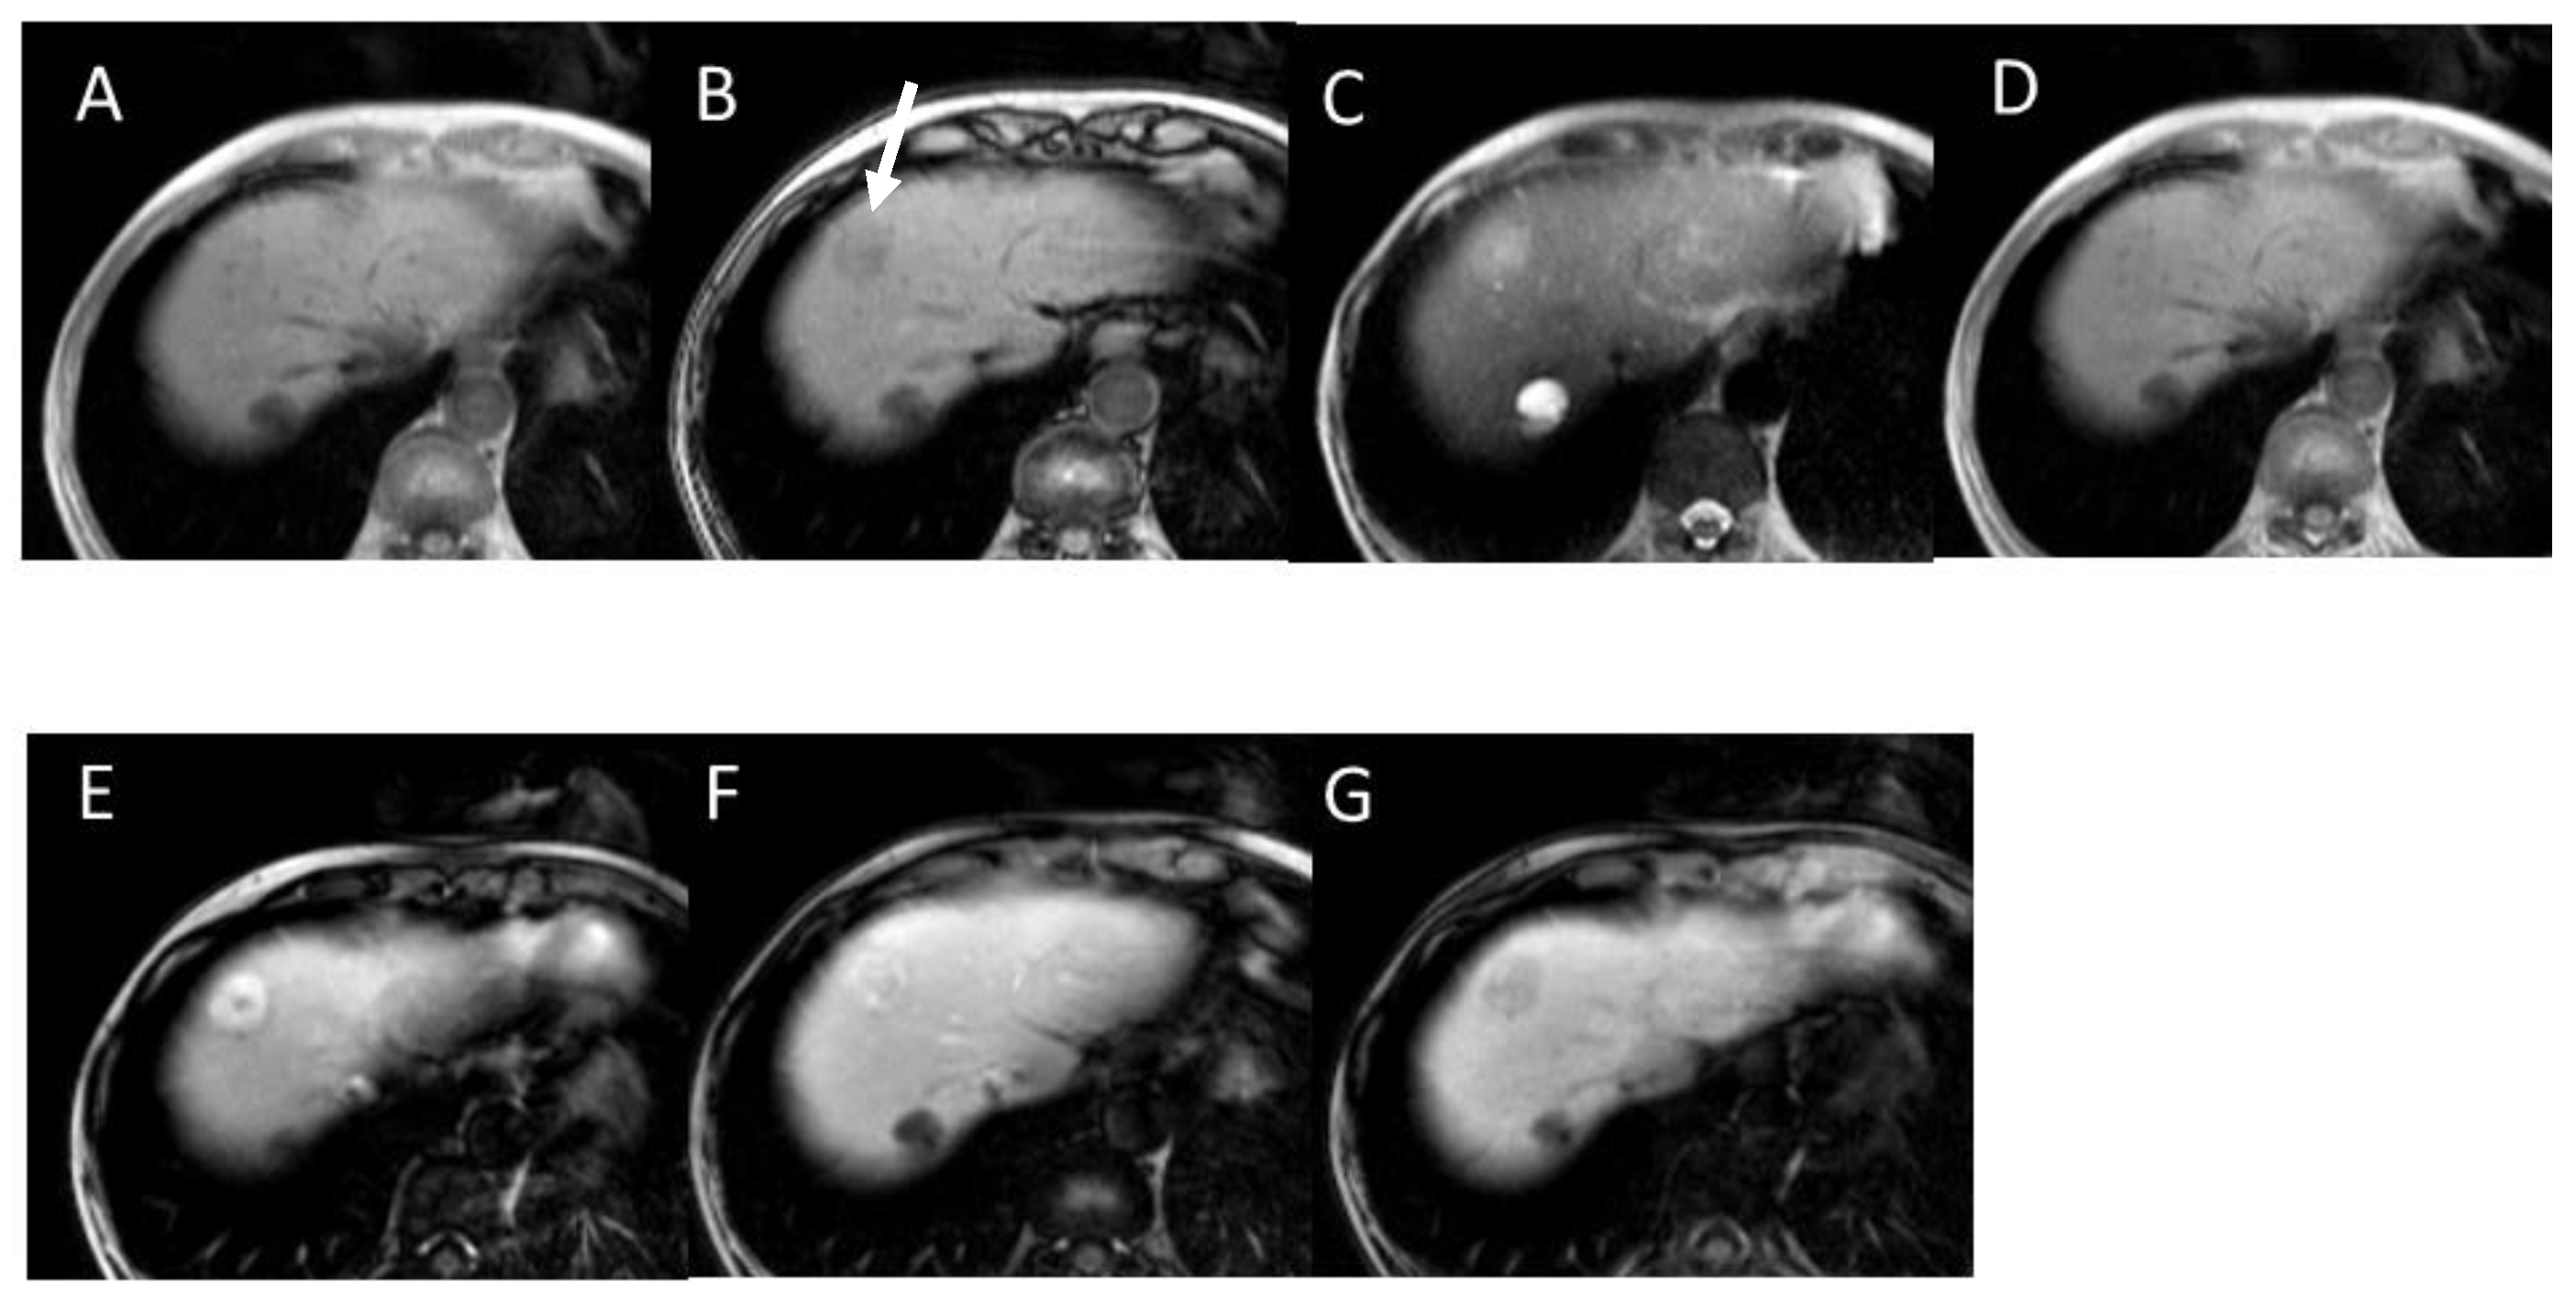

4.6. Fibrolamellar Hepatocellular Carcinoma (FL-HCC)

4.7. Combined Hepatocellular and Cholangiocarcinoma (cHCC-CCA)